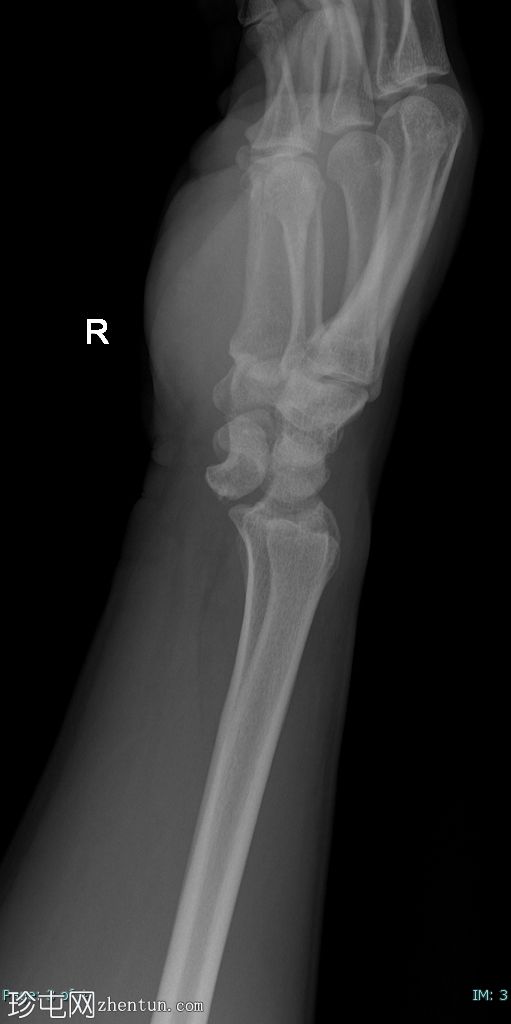

侧位片

月骨呈“饼状”移位,掌侧成角和移位,侧位片上呈“倾倒的茶杯”样外观。

侧位片上桡骨和头状骨对位正常。

尺骨茎突骨折移位。未见其他骨折。

腕关节处桡骨和尺骨对位正常。

软组织肿胀。